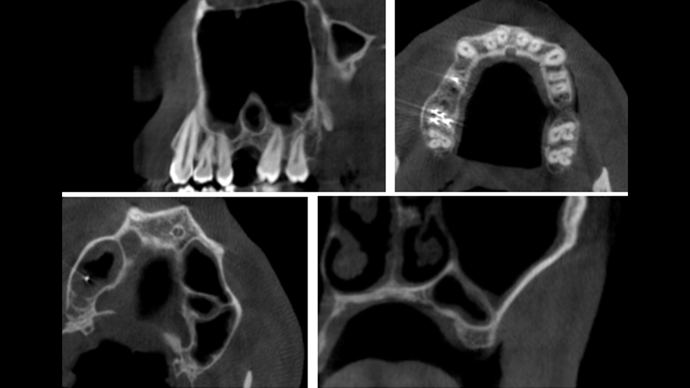

Clinical case: Installation of dental implants in complicated anatomic conditions using crest lifting methods

- Courtesy of Dr.Alexander Lysov, Russia -

Keywords

AnyRidge, complicated anatomic conditions, crest lift, MICA Kit, Dr. Alexander Lysov, bone regeneration, GBR, #26, maxillary posterior

AnyRidge implant system, MICA Kit